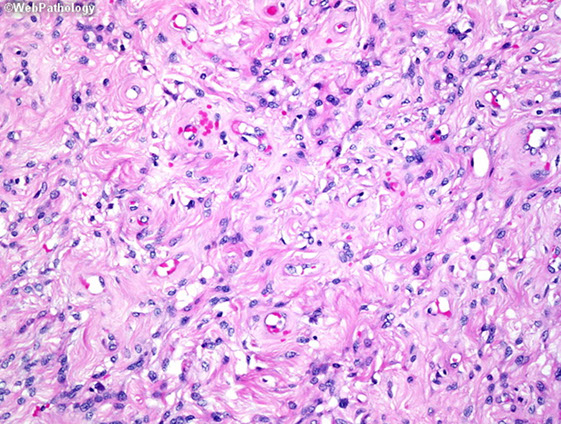

Alveolar soft parts sarcoma (ASPS)

Rare highly malignant neoplasm of deep ST (thigh and buttock in adults, head and neck in children) c well-defined nests separated by fibrous stroma in deep ST of thigh.buttock, mouth, mediastinum, thigh of young females

- 50% present c lung mets

Gross: well circumscribed, large gray-yellow c hemorrhage and necrosis up to 14 cm

Micro: well-defined organoid nests of large uniform polygonal cells c granular red cytoplasm, vesicular nuclei and large nucleoli

- cells separated by fibrous stroma

- has alveolar pattern if cells are discohesive

- no/rare mits, minimal pleomorphism; commonly invades vessels and has rhomboid crystalloids

Cyto: very similar to CCRCC

IHC: PAS+ diastase resistant (crystal structures on EM pathognomonic), desmin (1/2+ focally), MyoD1, nuclear TFE3

- negative vimentin, CK, chromogranin, synapto, S100 (1/4+), actin (1/10+)

Genes: unbalanced t(X;17)(p11.2;q25) fusing TFE3 transcription factor gene at Xp11 to a novel gene at 17q25 (ASPSCR1, at the ASP Locus); messed up chr 1, 5, 13, 17

Px: depends on size, 17q25 abnormality, stage, age; thought of as an indolent but fatal course (87% survival at 2 yrs; 18% @ 20 yrs)

- can have lung mets up to 3 decades later